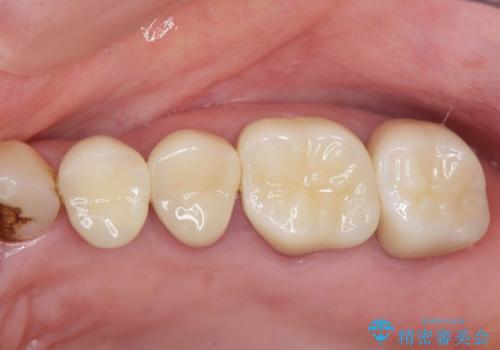

治療前に訴えられていた、痛みや違和感は消失し、しっかり噛めるようになったと喜んでいただくことができました。